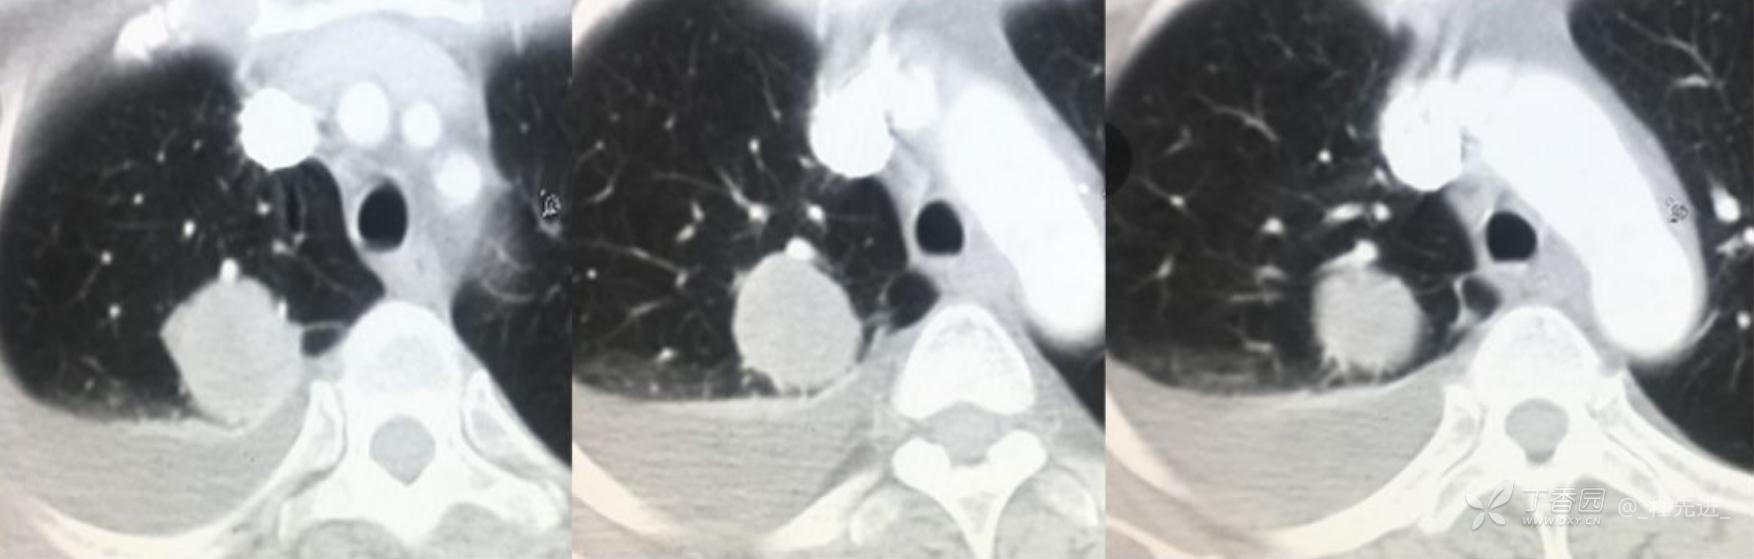

简要病史:乏力、纳差20余天,皮肤巩膜黄染半月偶有咳嗽,咳白痰,全身皮肤巩膜黄染。无咯血,无明显胸闷、胸痛,无明显气促,无发热及盗汗。精神欠佳,纳差,睡眠一般,二便正常